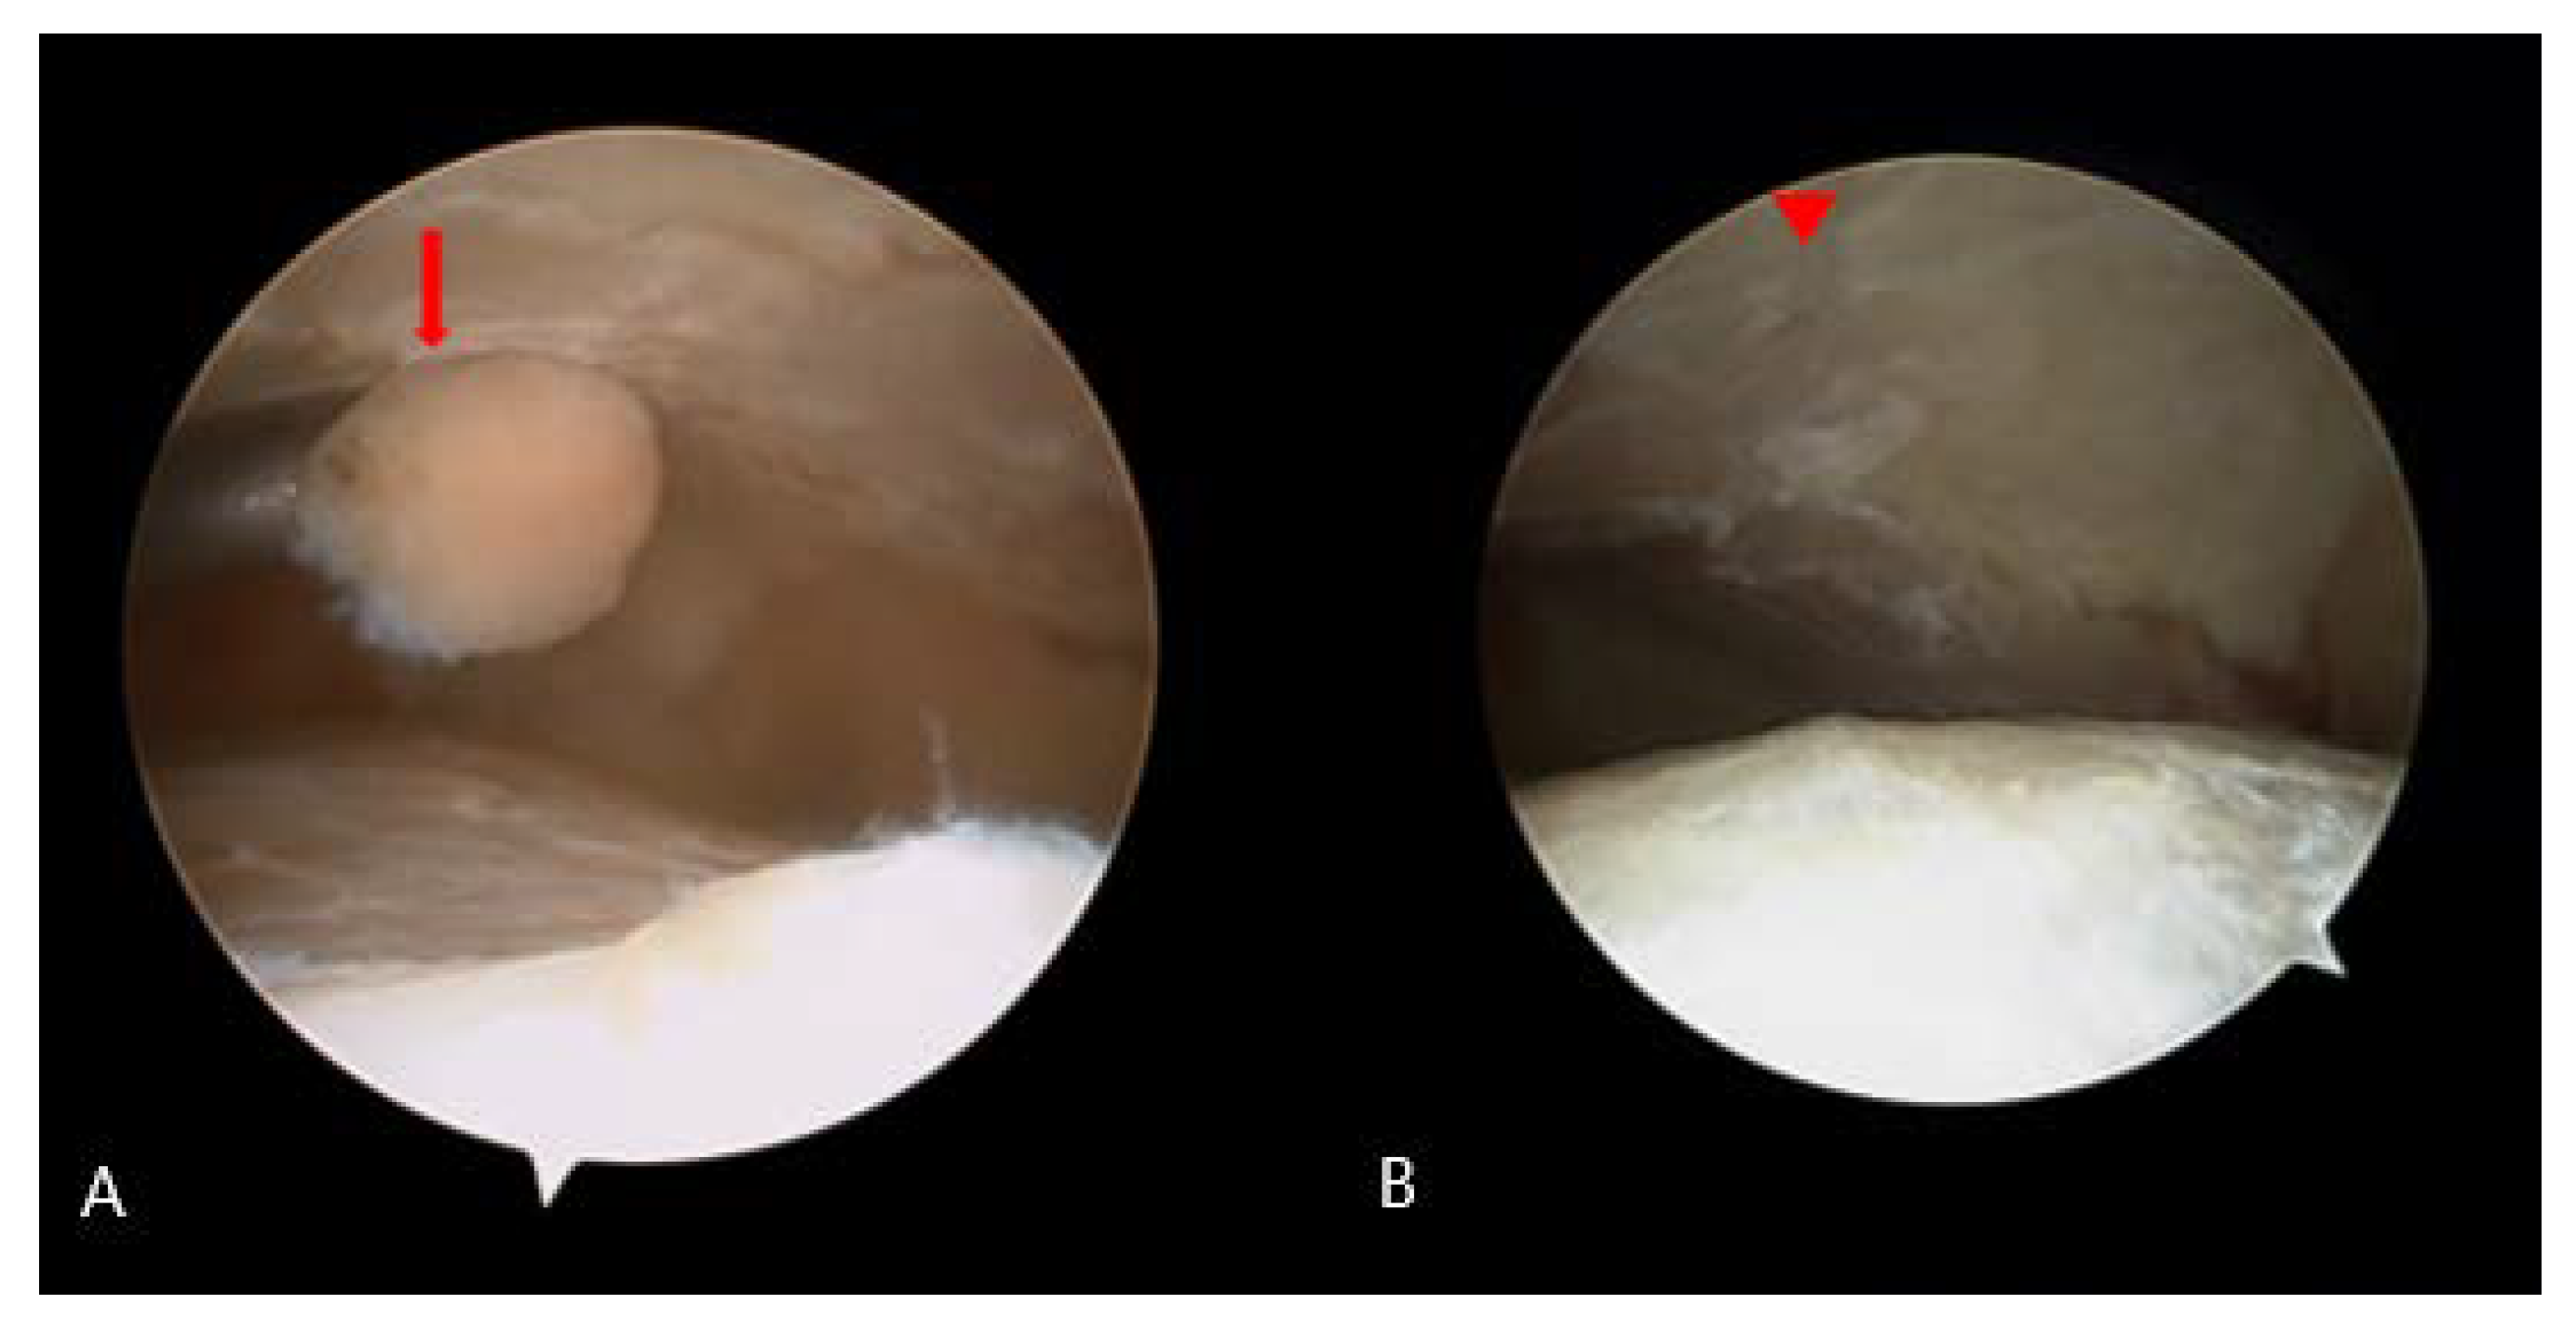

2.2. Surgical Procedure